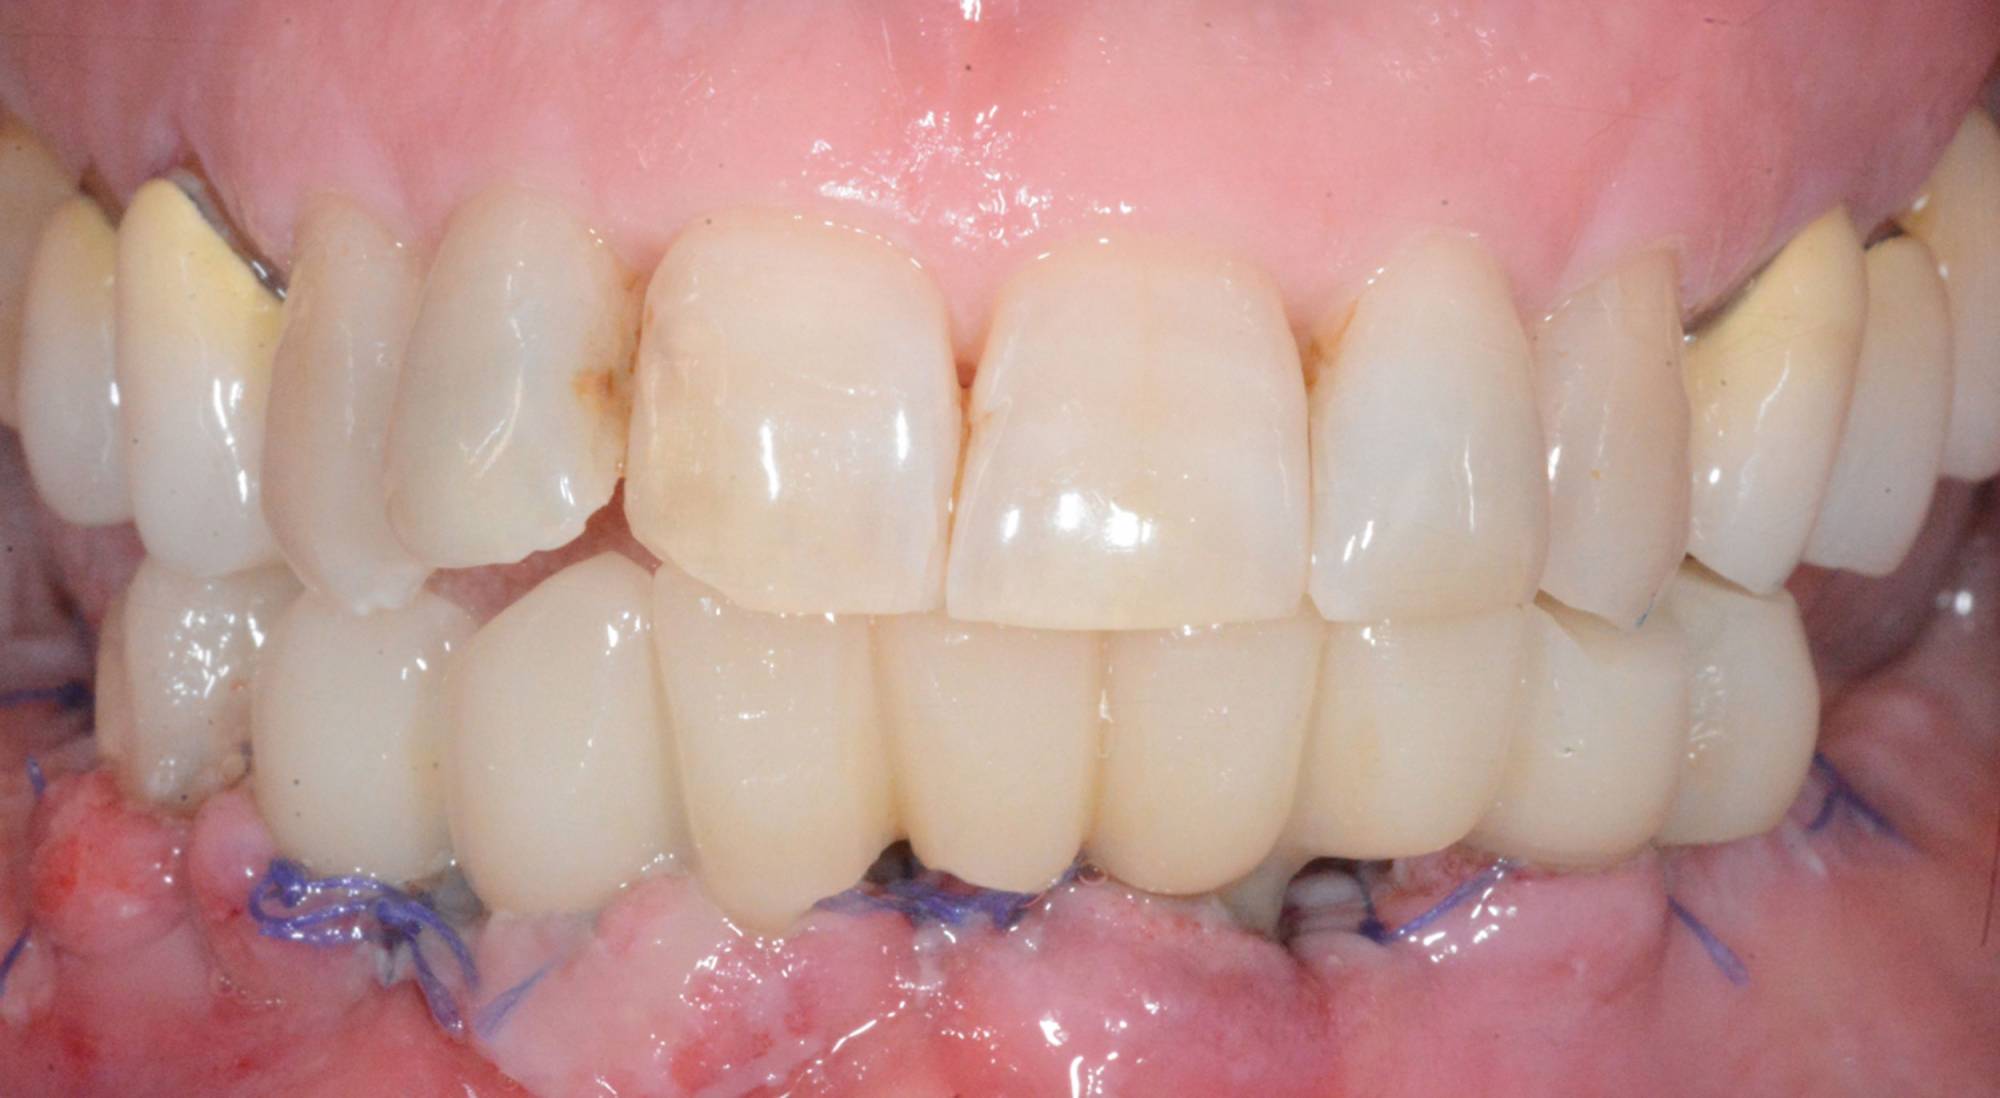

Tuttavia, in alcuni casi selezionati, è possibile protesizzare gli impianti subito dopo il loro posizionamento, nel giro di pochi giorni o addirittura nel corso della stessa seduta: questa tecnica è definita “carico immediato” e consente al paziente di entrare in Studio con la sua vecchia dentiera e di uscire il giorno stesso con una protesi fissa.